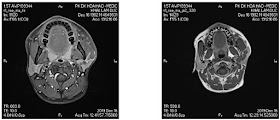

MRI confirmed a Kikuchi - Fujimoto disease, necrotizing histiocytic lymphadenitis.

But biopsy result was a Schwannoma of the left facial nerve sheath.